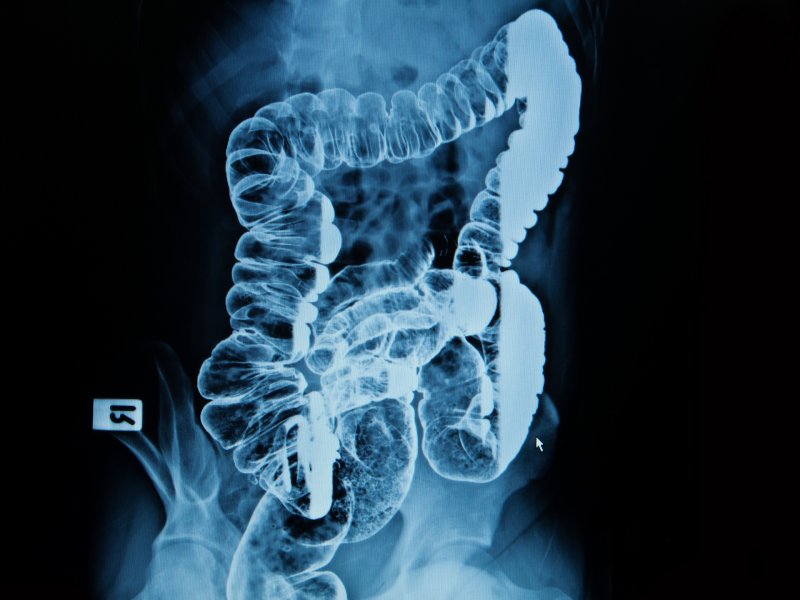

Badanie jelita

Adalimumab jest w pełni ludzkim monoklonalnym przeciwciałem anty-TNF-alfa klasy IgG1. Jest stosowany w ciężkich postaciach nieswoistych zapaleń jelit,...